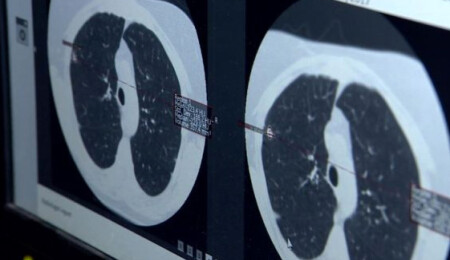

Turan, "Virüsün şiddeti devam ediyor. Yarattığı akciğer hasarı inanılmaz. Bir yoğun bakım hekimi olarak söyleyebilirim ki gördüğümüz akciğer filmleri ve tomografileri olayın şiddetinin oldukça fazla olduğunu ve bu hasta gruplarının da zannedildiği gibi çok ileri yaş olmadığını; yaşamı içerisinde aktif yaşamını devam ettiren bireylerin de çok ağır klinik tablolarla bize başvurduğunu söylemek zorundayım" dedi.

"Hastanın akciğer tomografileri ve filmlerini gördüğünüz zaman 'Bu hastalar acaba nasıl nefes alabiliyor?' diyebileceğiniz görüntüler. Bizim halkımızdan tek beklentimiz kurallara uysunlar ve yoğun bakıma ihtiyaç duyulmasın; yoğun bakım ortamı gerçekten zor bir ortam, hastalar için de çok sıkıntılı bir yer. Kendilerinin buna ihtiyaç duymamaları için kısıtlamalara uyulmasını tavsiye ediyorum."